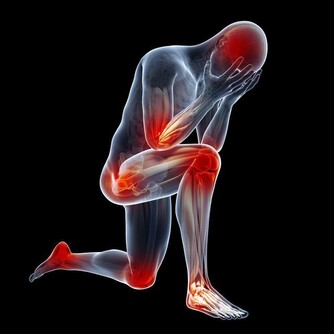

女人更年期症狀到來一般表現為:失眠、頻尿、腰酸背痛渾身不適,更年期婦女要當心,這些恐怕都是更年期症狀,需要就醫治療。

西紅柿專家表示由於更年期症狀多元,包含心悸、頻尿、失眠等,

他提出「3不5時」快篩法,「更年期婦女3不5時腰酸背痛、每晚頻尿如廁超過3次,